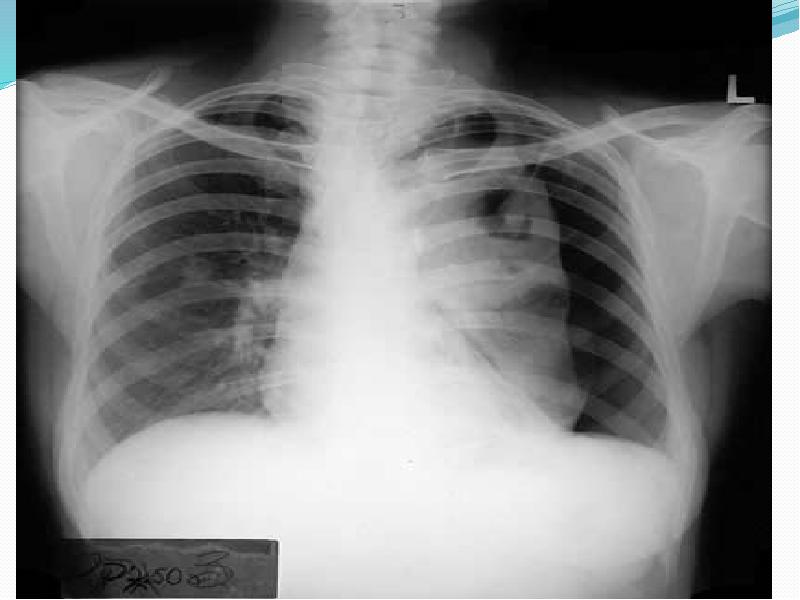

- 17. Асқынулары Ерте Пневмоторакс (үдемелі, клапанды) Гемоторакс Жүрек тампонадасы Респираторлы дистесс-синдромы Хилоторакс

- 23. Инструментальды тексеру әдісі Рентгенологиялық тексеру (рентгенография, рентгеноскопия) Компьютерлік томография УДЗ